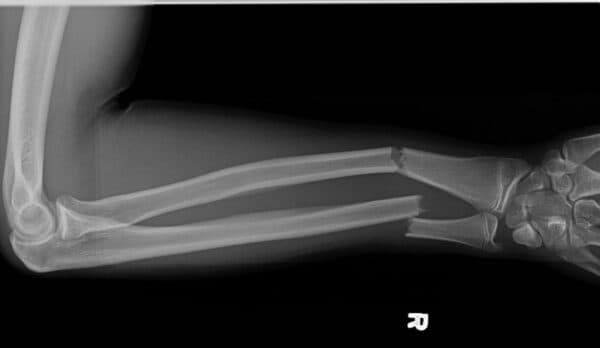

– Xuất hiện tình trạng cẳng tay bị ngắn lại, gập góc, bị xoắn vặn hoặc khớp biến dạng, ngón tay bị tê, không cử động hoặc hơi xanh tím ở đầu ngón tay.

– Gãy xương kín (dạng gãy xương đơn giản): là trường hợp xương gãy nhưng không tạo ra vết thương hở ở da.

– Gãy xương hở (dạng gãy xương hỗn hợp): là trường hợp xương bị gãy xuyên qua da và tạo thành vết thương hở.

– Gãy xương hoàn toàn là trường hợp xương bị gãy/nghiền thành 2 mảnh rời ra hoặc thành nhiều mảnh.

– Gãy xương không hoàn toàn là trường hợp xương chỉ bị tổn thương một phần mà không bị mất hoàn toàn tính liên tục.